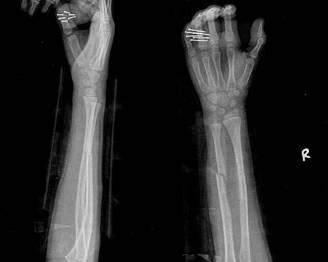

摘要:最新尺橈骨融合方法展現(xiàn)骨頭間的奇妙和諧與友情力量。通過先進的醫(yī)療技術(shù),尺骨和橈骨之間的融合得到顯著改善。這種方法不僅提高了治療效果,還展現(xiàn)了人體骨骼之間的和諧關(guān)系。憑借友情和信念的力量,醫(yī)學(xué)界不斷突破,為患者帶來福音。

經(jīng)過醫(yī)生的診斷,小明被確診為尺橈骨融合,這是一種骨骼疾病,會導(dǎo)致尺骨和橈骨無法正常活動,聽到這個消息后,小明和他的朋友們都感到有些緊張和害怕,但他們并沒有放棄,而是選擇相互鼓勵,共同面對這個挑戰(zhàn)。

在醫(yī)生的介紹下,他們了解到了一種最新的尺橈骨融合治療方法——通過微創(chuàng)手術(shù)進行骨骼融合的新技術(shù),這種方法不僅減少了手術(shù)風(fēng)險,還能更快地恢復(fù)活動能力,雖然小明感到害怕,但他的朋友們一直陪伴在他身邊,給予他勇氣和力量。